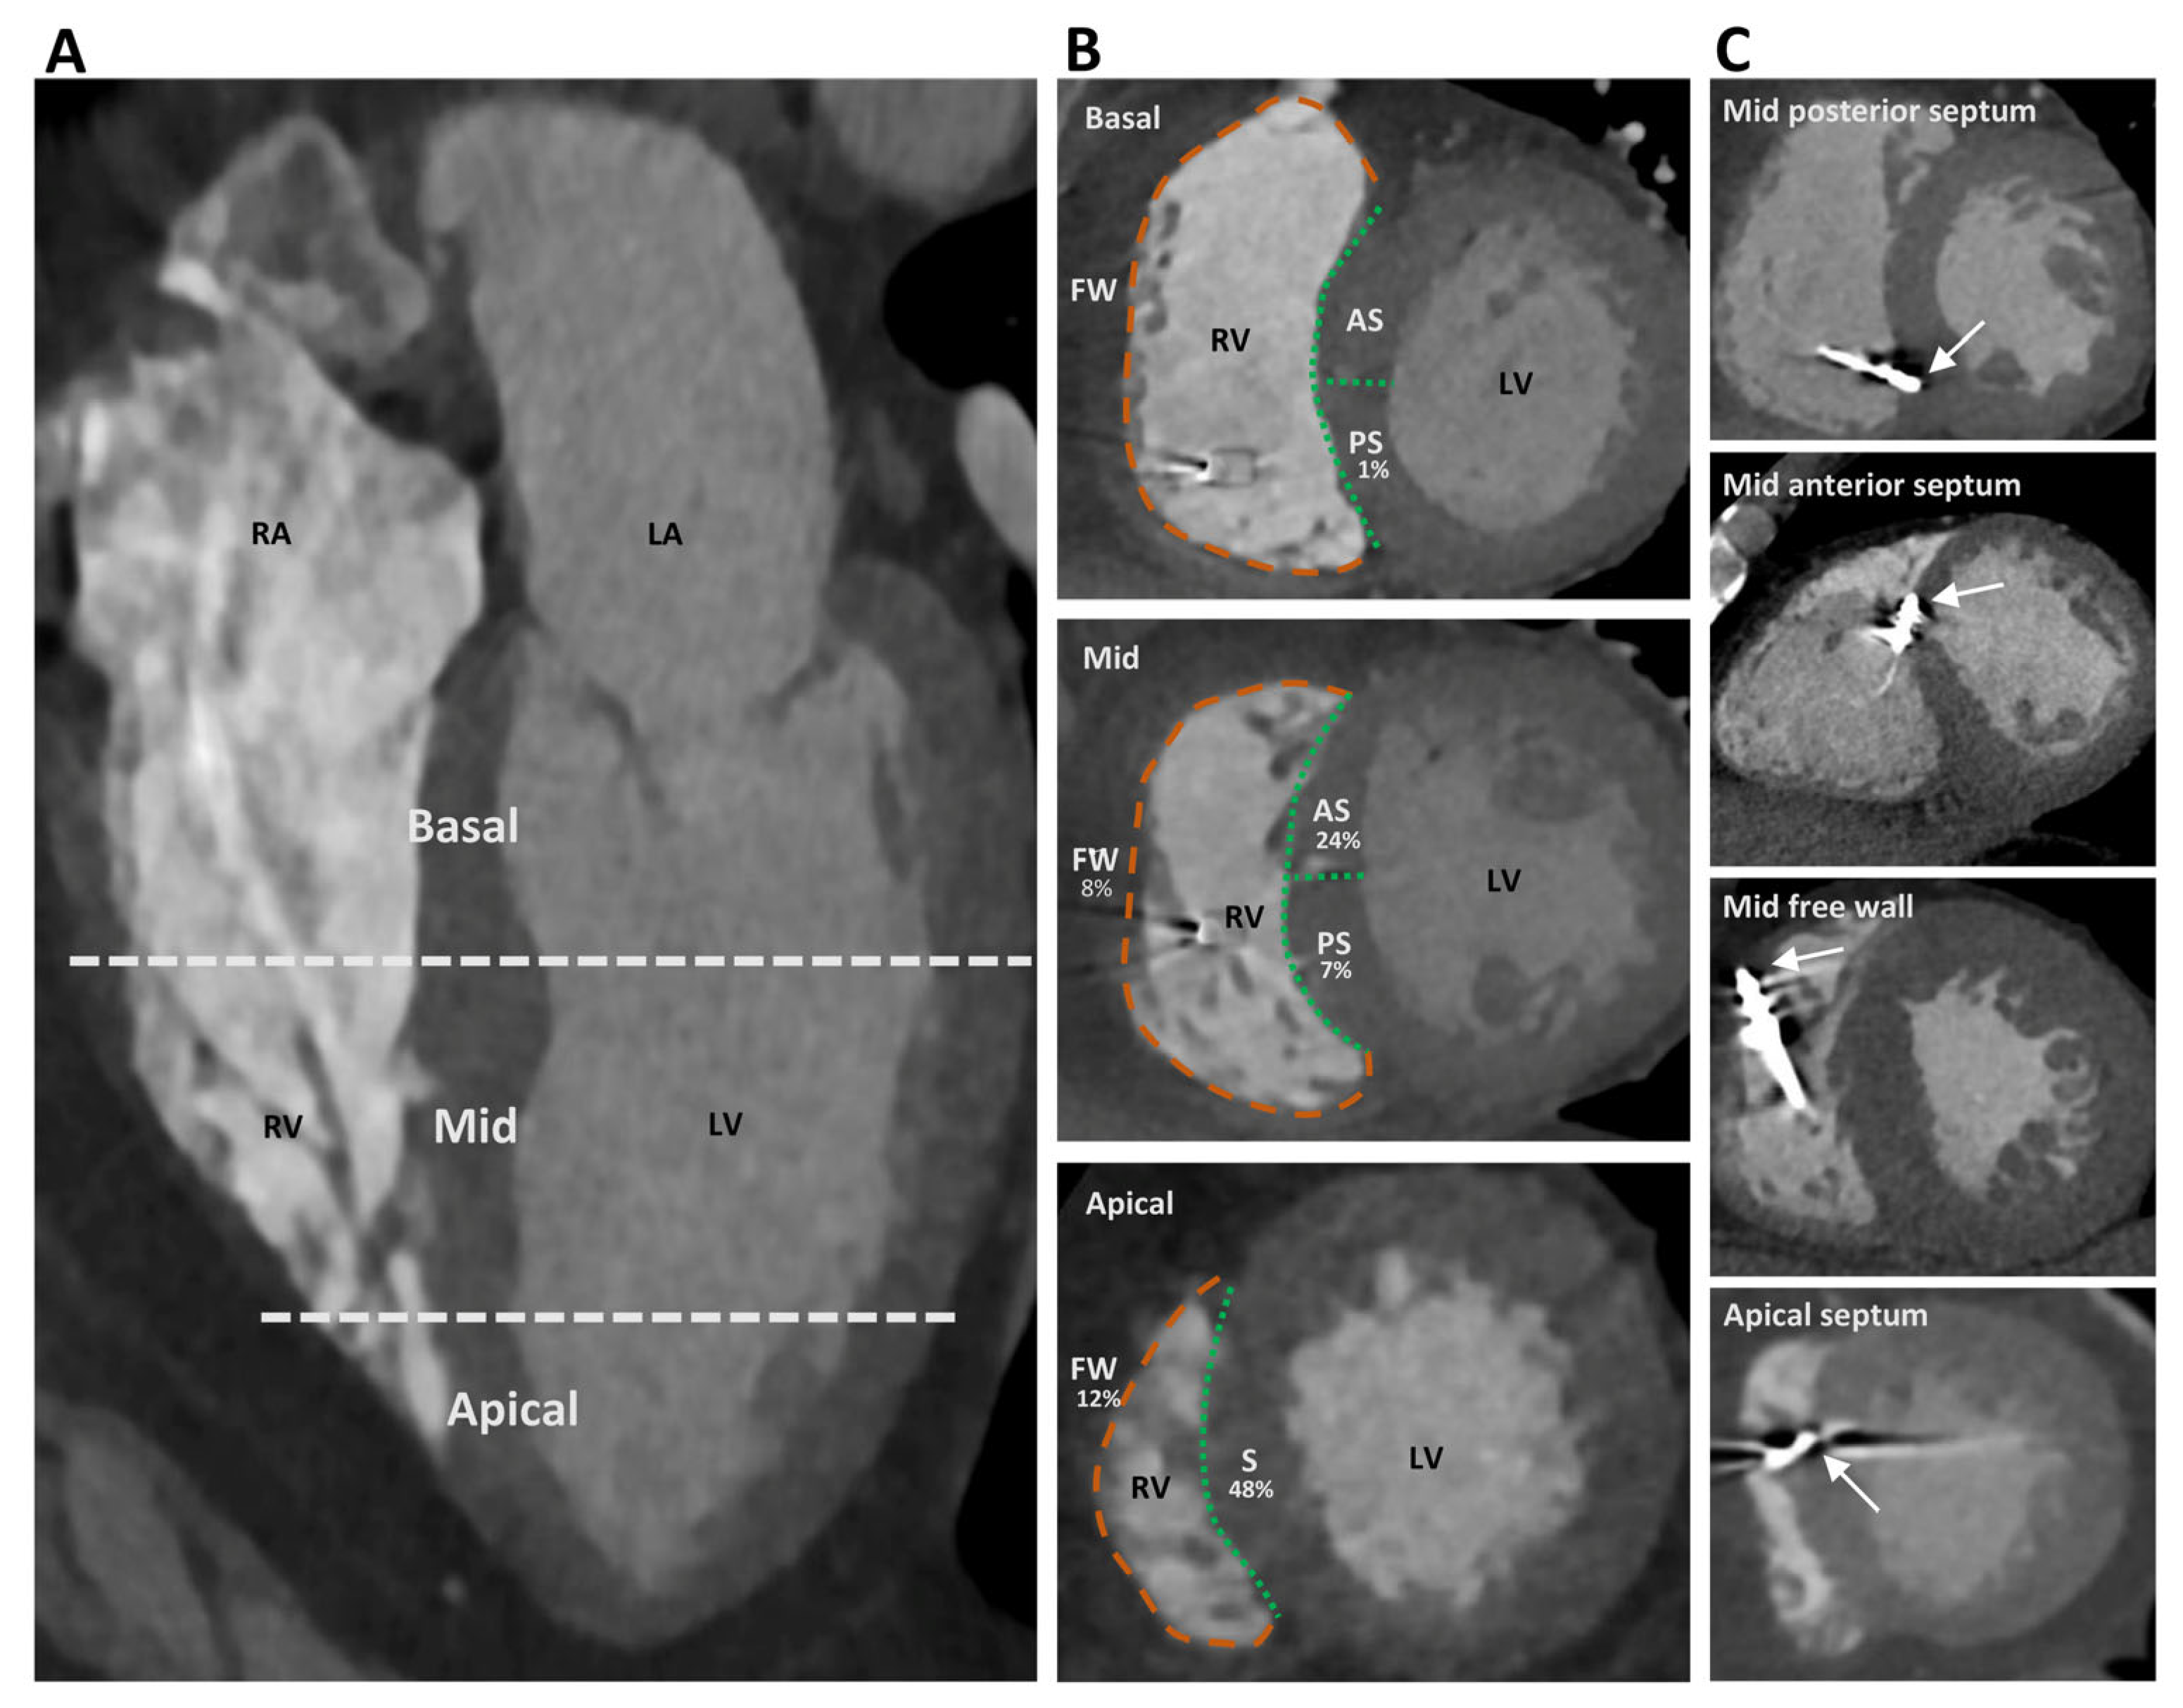

2.4. Cardiac Computed Tomography—Acquisition and Analysis

3.2. CT-Determined RV Lead Position